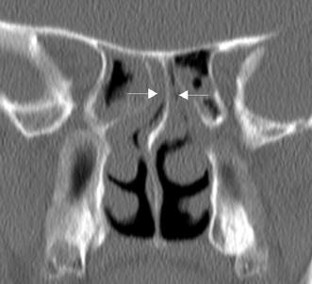

Radiological imaging of inflammatory lesions in the nasal cavity and paranasal sinuses

Paranasal sinus development and pneumatisation variants are described, and rhinosinusitis and different patterns of inflammatory sinonasal diseases are reviewed. Other inflammatory sinonasal diseases, e.g., fungal sinusitis, mucocele, pyocele and sinonasal manifestations in systemic diseases, are briefly described. Computed tomography (CT) is the primary modality in diagnosing and mapping suspected inflammatory sinonasal disease. Magnetic resonance (MR) imaging is complementary to CT if fungal sinusitis, pyocele or malignancy are suspected.